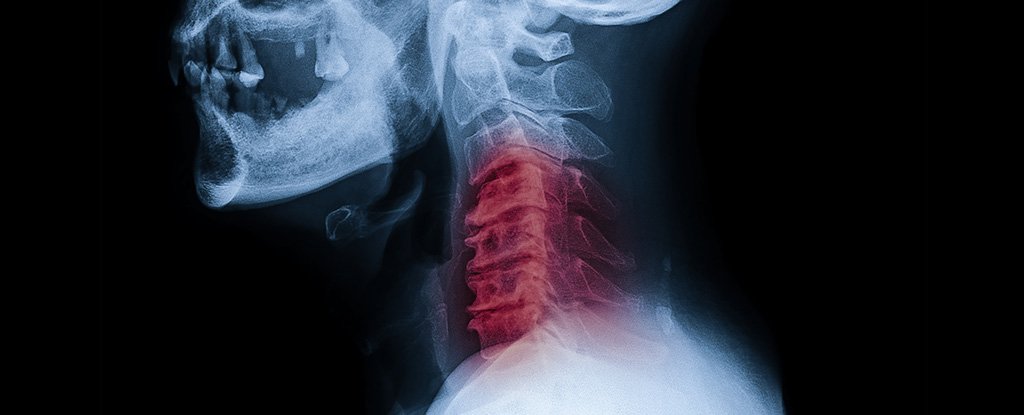

▼喬許被岳父帶往醫院急診,到院時已半身麻掉、有複視症狀。院方血管攝影結果發現,他的頸動脈分離,造成腦溢血,趕緊注射TPA靜脈血栓溶解劑治療。後來又轉至大醫院的加護房,待了4天才來到普通房。

▼主治醫生指出,喬許應該是在扭轉脖子時,牽扯到了頸部動脈,才會導致動脈分離,血栓在患部形成後,堵塞了血管。他也提醒,扭轉脖子並沒有什麼正確方式,一般人不要輕易嘗試。